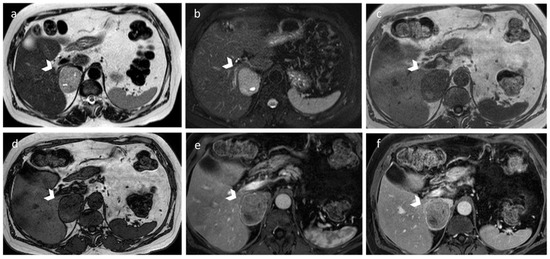

2.3. Adrenal Hyperplasia